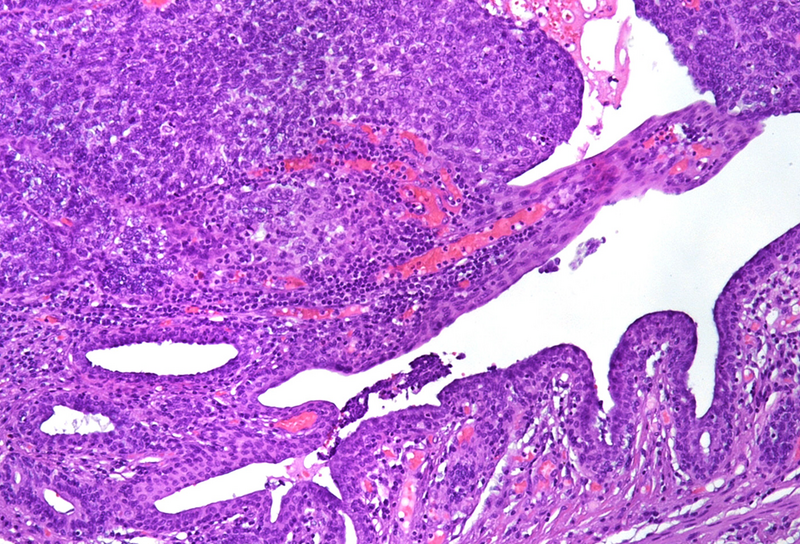

Histological examination showed a solid neoplasm with a predominantly nodular to lobulated growth pattern, frequently exhibiting peripheral palisading and central areas of comedonecrosis, located in the anal transitional zone (Panel A). The neoplastic cells were small to medium-sized, with scant cytoplasm, hyperchromatic nuclei, and inconspicuous nucleoli (Panel B). Glandular differentiation was minimal to absent (Panel C). The lesion showed focal connection with the overlying surface epithelium, which exhibited areas of papillary architecture with downward extension of neoplastic nests into the underlying stroma (Panel D).  The overall morphological features were consistent with a poorly differentiated carcinoma, not clearly indicating glandular and/or squamous differentiation.